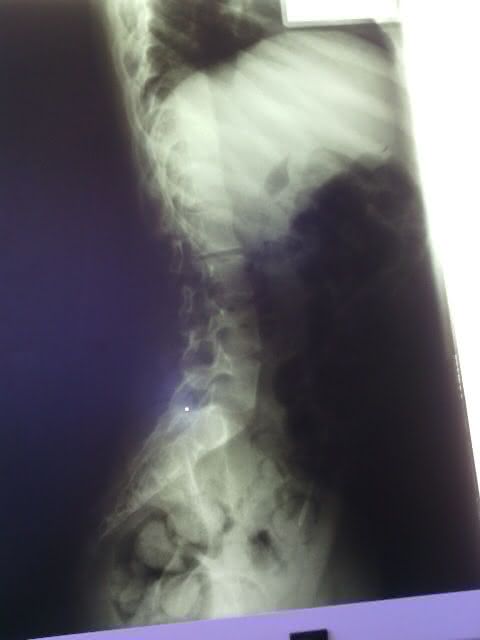

A equipe do portal visitou a residência do vigilante e da professoram que dedicam suas vidas ao pequeno Mateus Domingos dos Santos de 15 anos, que sofre de escoliose que é o encurvamento anormal da coluna vertebral, que provoca dor lombar e nas costas e pode morre caso não consiga realizar uma cirurgia nos próximos meses.

Durante duas horas, os pais contaram ao radialista João Miguel toda história de dor e sofrimento, que aumentou no decorrer dos dias com a notícia, que a escoliose vem atrofiando alguns órgãos que pode levar a morte do seu filho.

- Raio -X da coluna